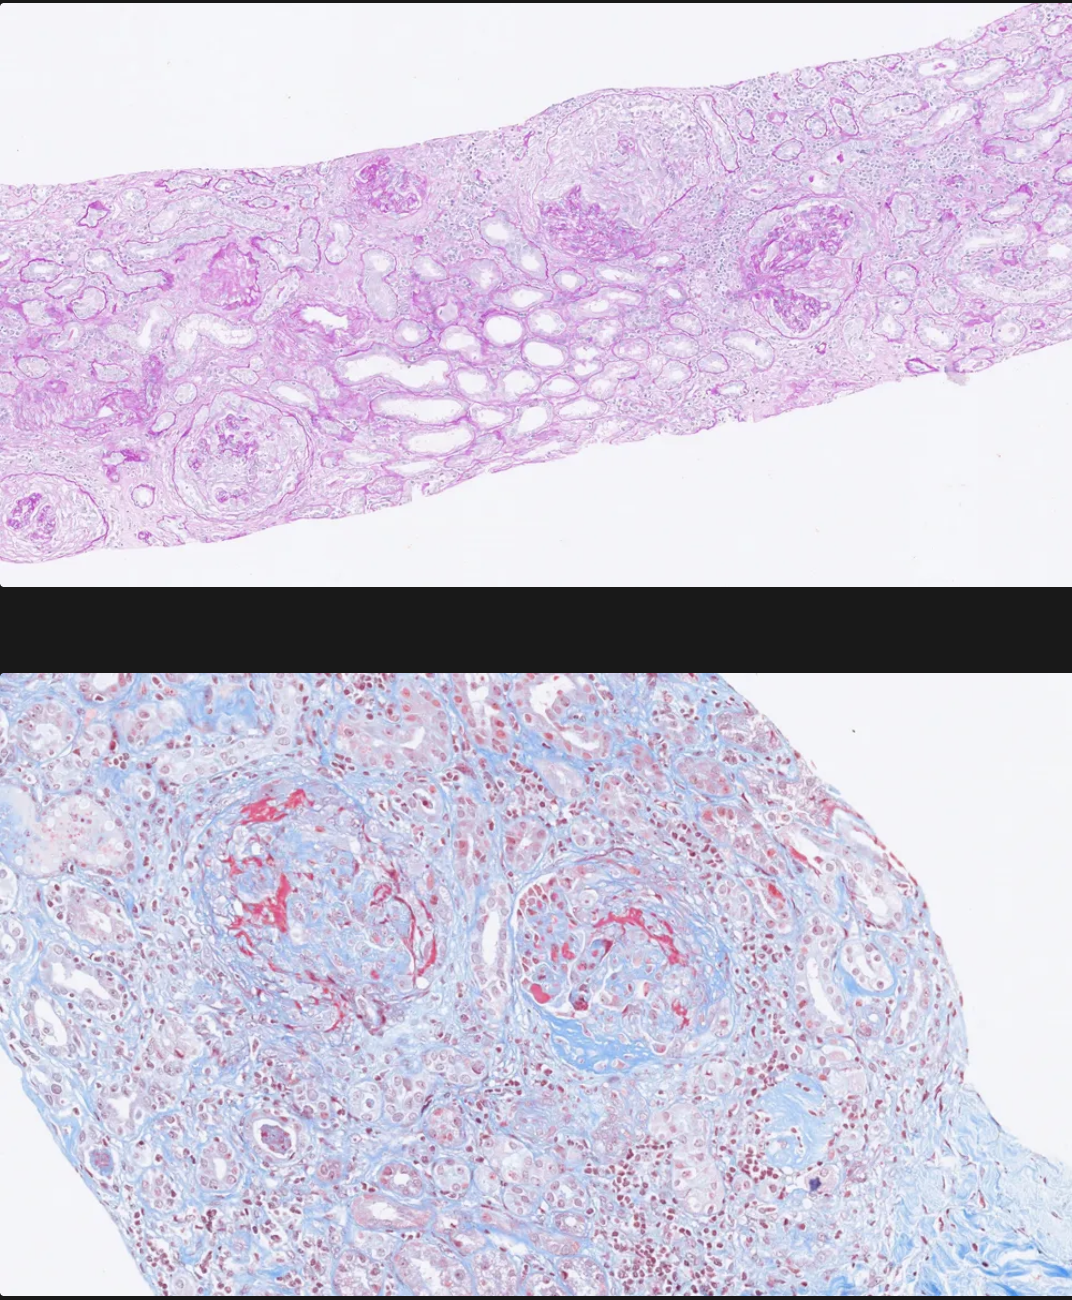

Qué se aprecia en la imágen y a que patologia está asociada?

Necrosis focal y segmentaria y formación de semilunas en el espacio de Bowman.

Enfermedad anti-GBM Good pasture syndrome

Qué se puede ver en la inmunofluorescencia? que patrón sigue? a que enfermedad está asociada?

Se ven: anticuerpos anti-GBM y complemento (IgG, a veces IgA)

Patrón: lineal

Enfermedad anti-GBM (Enfermedad de good pasture)